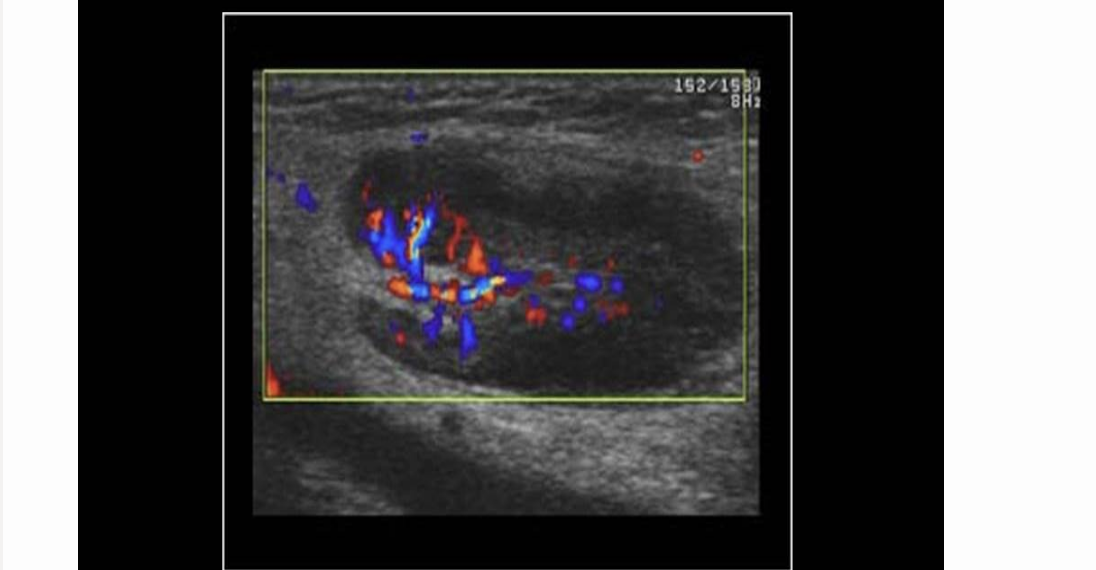

pt has groin pain 3 days after undergoing right femoral artery angioplasty. this is right groin AOI. what should you put in your report

.

a) pseudoaneurysm that’s nearly thrombosed

b) abn enlarged LN

c) pseudoaneurysm requiring immediate attention

d) normal LN